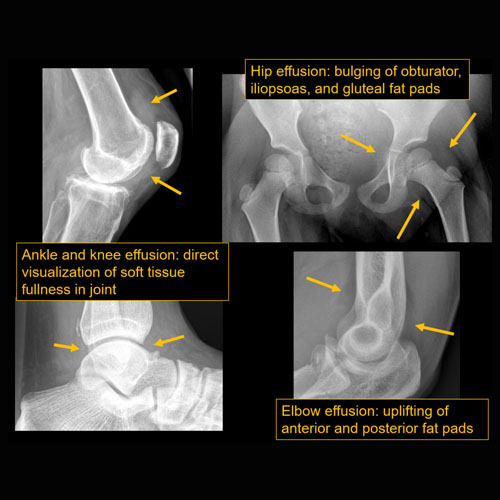

There is a joint effusion. |